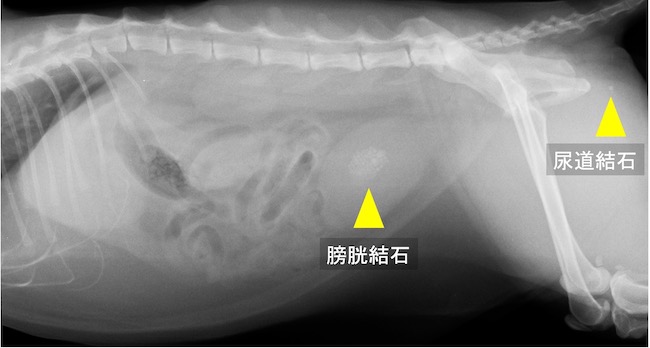

雄猫の膀胱結石および尿道結石。排尿障害により急性腎障害を呈していた。